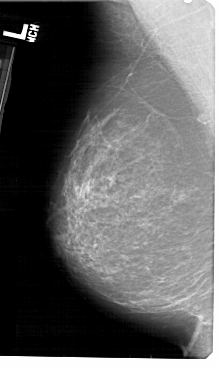

A_1418_1.LEFT_MLO

LEFT_MLO LINES 5491 PIXELS_PER_LINE 3256 BITS_PER_PIXEL 12 RESOLUTION 43.5 NON_OVERLAY